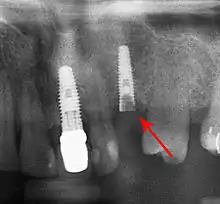

Long-term failures are due to either loss of bone around the tooth and/or gingiva due to peri-implantitis or a mechanical failure of the implant. Because there is no dental enamel on an implant, it does not fail due to cavities like natural teeth. While large-scale, long-term studies are scarce, several systematic reviews estimate the long-term (five to ten years) survival of dental implants at 93–98 percent depending on their clinical use.[1][2][3] During initial development of implant retained teeth, all crowns were attached to the teeth with screws, but more recent advancements have allowed placement of crowns on the abutments with dental cement (akin to placing a crown on a tooth). This has created the potential for cement, that escapes from under the crown during cementation to get caught in the gingiva and create a peri-implantitis (see picture below). While the complication can occur, there does not appear to be any additional peri-implantitis in cement-retained crowns compared to screw-retained crowns overall.[68] In compound implants (two stage implants), between the actual implant and the superstructure (abutment) are gaps and cavities into which bacteria can penetrate from the oral cavity. Later these bacteria will return into the adjacent tissue and can cause periimplantitis.